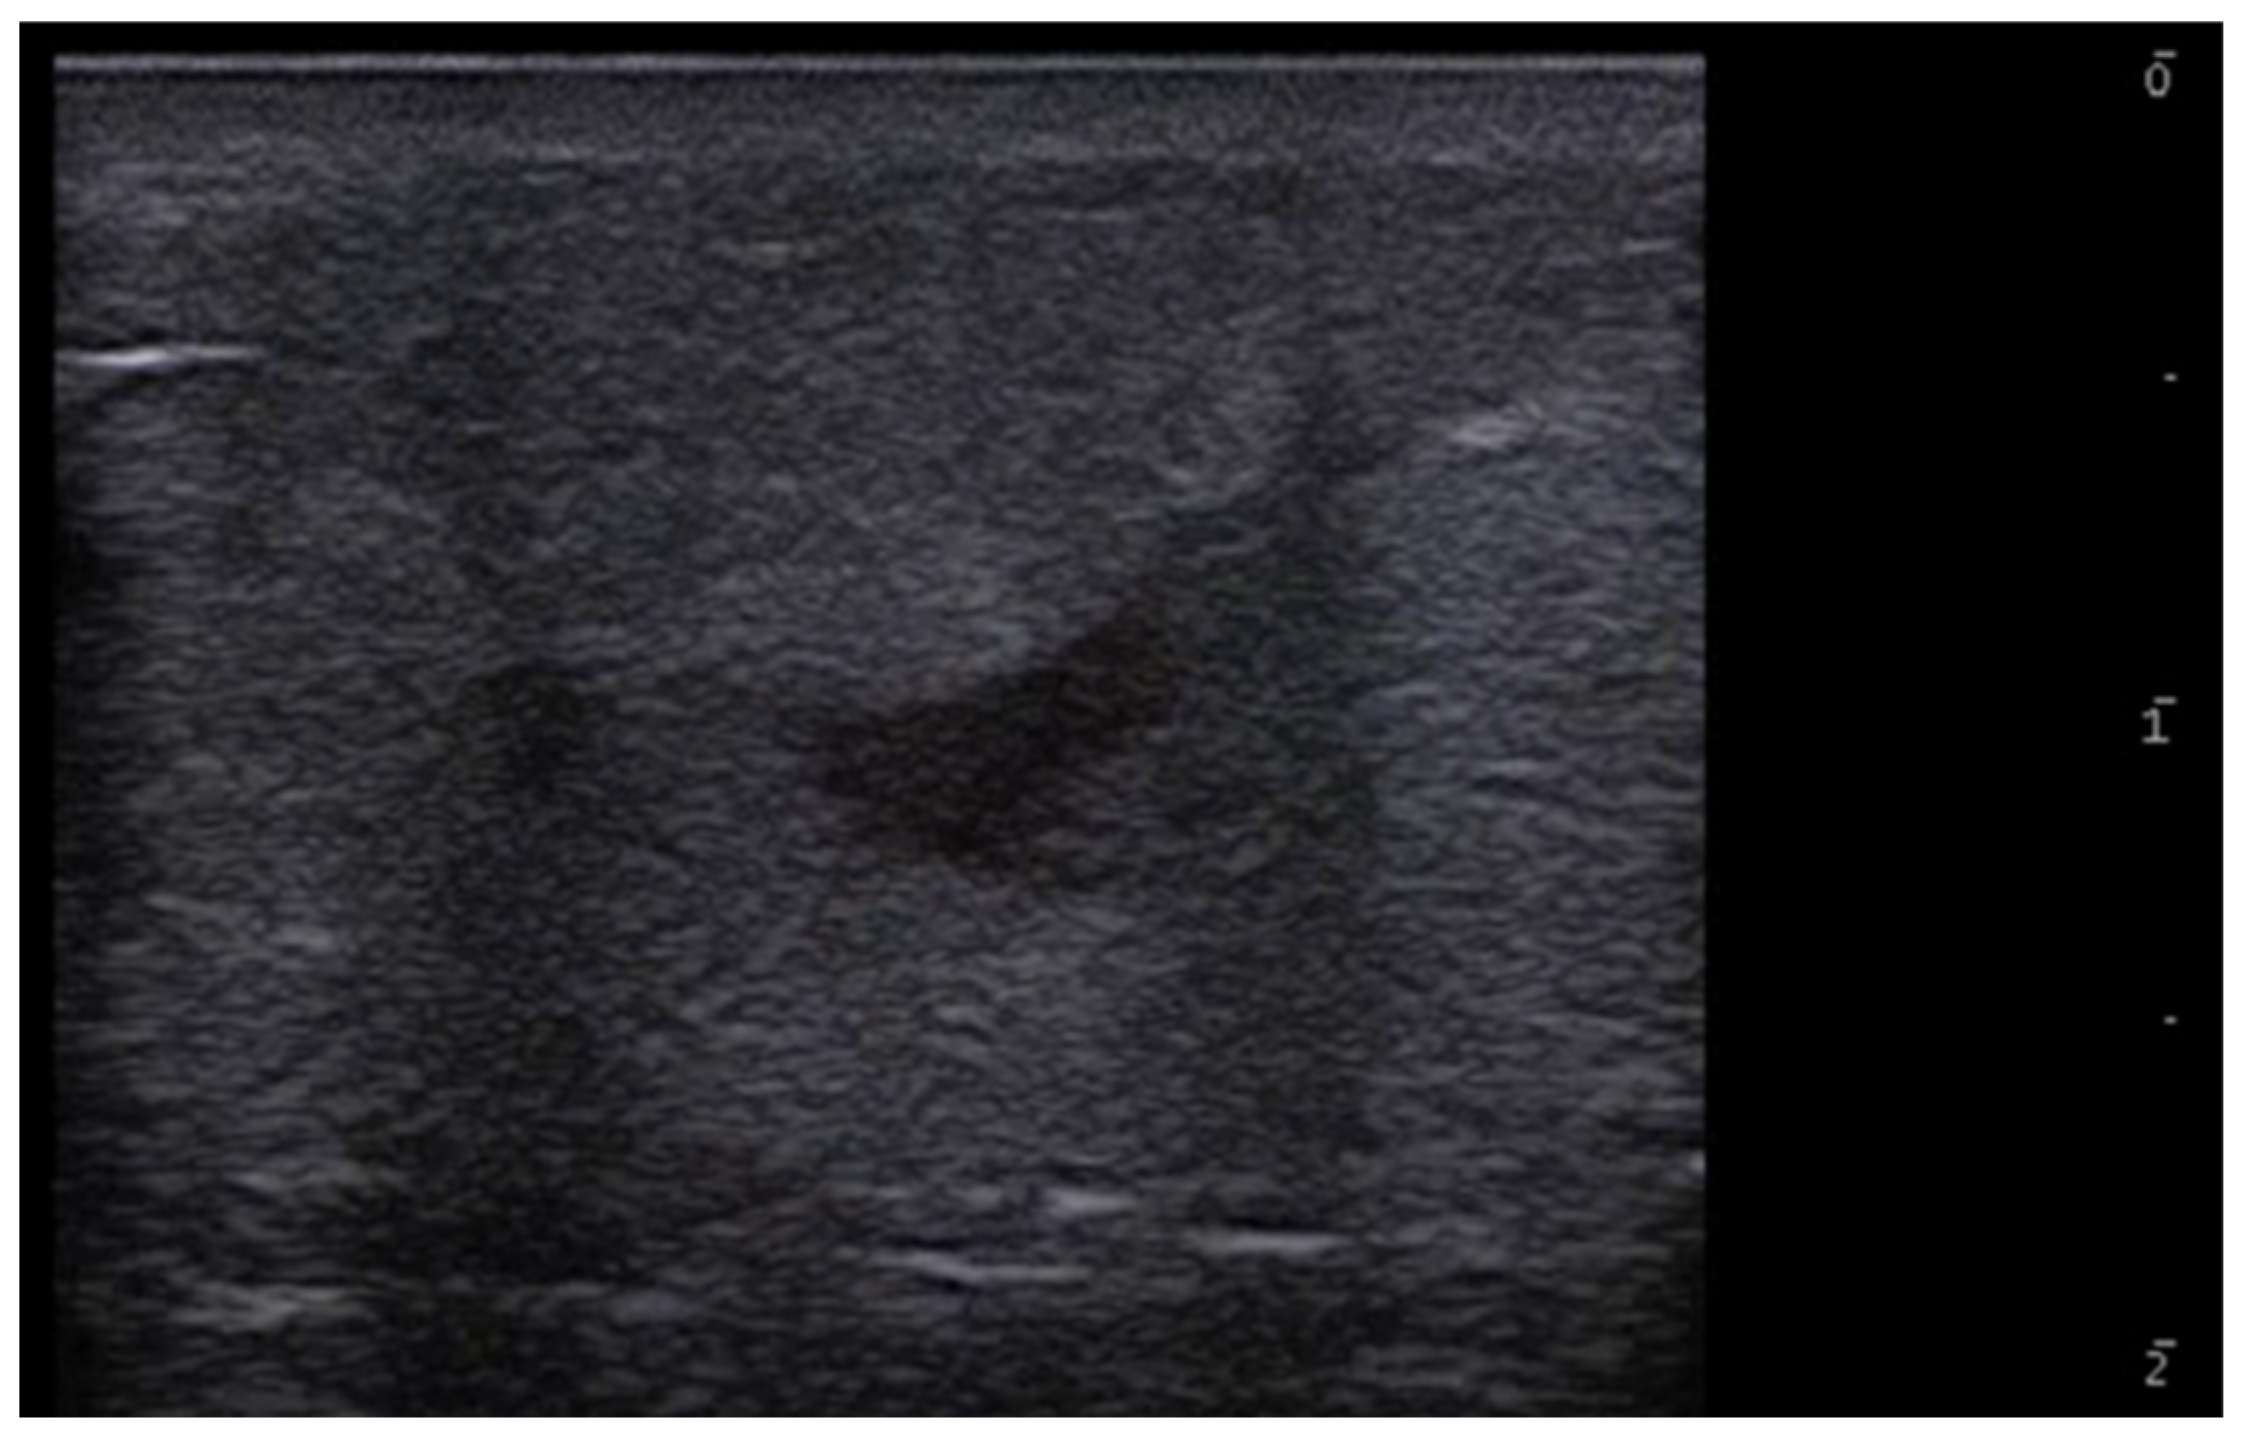

- Gonzalez, C.; Wortsman, X. How to Start on Dermatologic Ultrasound: Basic Anatomical Concepts, Guidelines, Technical Considerations, and Best Tips. Semin. Ultrasound CT MRI 2024, 45, 180–191. [Google Scholar] [CrossRef] [PubMed]